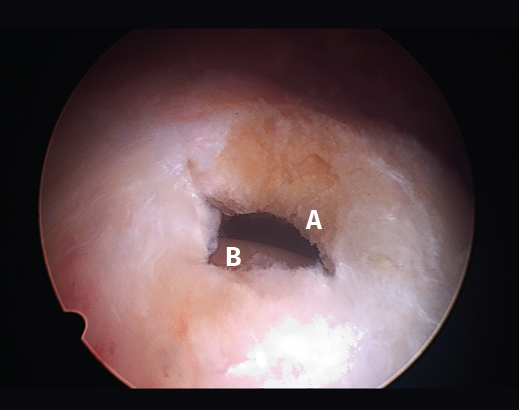

Figura 1. Rotura en forma creciente. A: acromion; B: rotura en forma de semiluna del tendón supraespinoso.

Figura 5. Rotura de tipo C1. A: rotura pequeña de espesor completo del supraespinoso; B: cabeza humeral.

Sin embargo, las clasificaciones basadas en el tamaño de la rotura deben ser bidimensionales, ya que la visión unidimensional puede ser engañosa, al mostrar el tamaño de la rotura solo desde el plano anteroposterior(4). Por esta razón, proponemos el sistema de clasificación del manguito posterosuperior sugerida por Snyder, que aporta información no solo del tamaño, sino del número de tendones afectados y la presencia de tejido cicatricial(7). En las lesiones de tipo C1 la lesión atraviesa todo el espesor del tendón y en el eje transversal es pequeña y punzante (Figura 5). Las de tipo C2 son roturas de espesor completo pero la distancia entre los extremos de la rotura es menor de 2 cm con escasa retracción (Figura 6). En las de tipo C3 la rotura afecta en sentido transversal entre 3 y 4 cm con mayor retracción implicando 2 tendones (Figura 7). Y las de tipo C4 son la rotura masiva del manguito de los rotadores con una afectación de espesor completo de toda la anchura de 2 o más tendones asociando importante retracción (Figura 8).